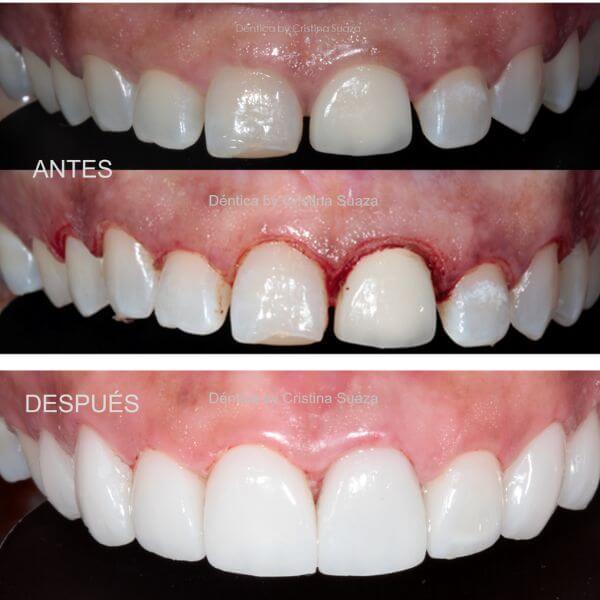

Dentica by Cristina Suaza

Odontólogo Bogotá

Antes y después de un recorte de encías para alargar los dientes y mejorar la armonía de la sonrisa, realizado en D…